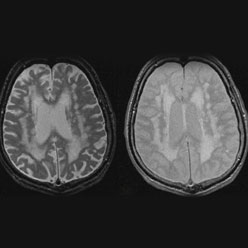

Embolic Strokes of Undetermined Source (ESUS)

Cryptogenic (“of mysterious cause”) ischemic strokes comprise about 25% of all ischemic strokes in recent studies. There is strong evidence that most cryptogenic strokes are embolic, with the thrombus originating from any of several well-established potential embolic sources, including minor-risk or covert cardiac sources, veins via paradoxical embolism, and non-occlusive atherosclerotic plaques in the aortic arch, cervical or cerebral arteries. The novel pragmatic construct of “embolic strokes of undetermined source” has been proposed since an embolic mechanism is likely, but the embolic source is uncertain. Because emboli consist mainly of thrombus, it is hypothesized that anticoagulants will reduce recurrent brain ischemia more effectively than antiplatelet agents.